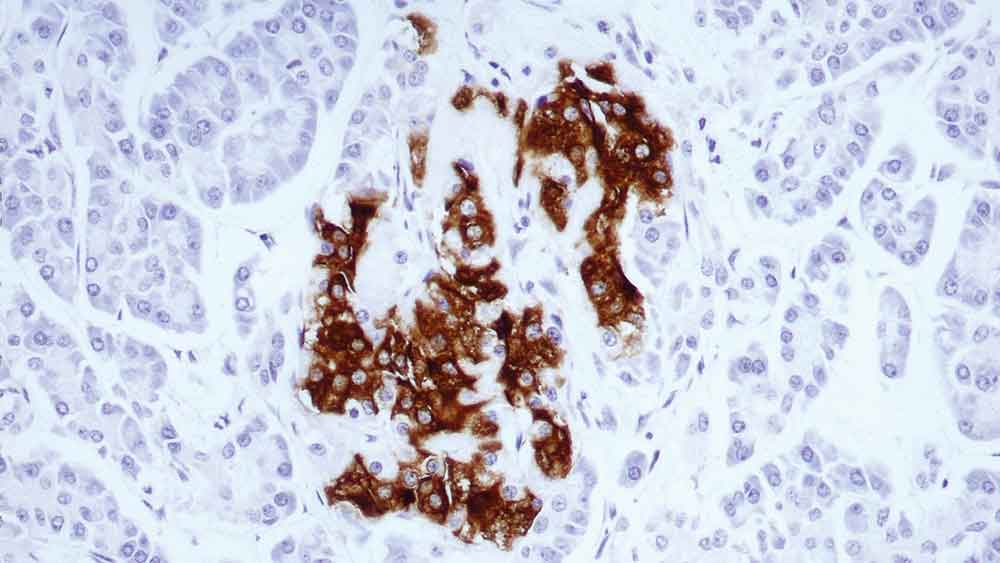

Human small bowel: immunohistochemical staining for Alpha Smooth Muscle Actin. Note cytoplasmic staining of the muscularis mucosa, vascular walls and smooth muscle fibers in the lamina propria. SMA: clone clone αsm-1

Cytoplasmic actins are part of the microfilament system of cytoskeletal proteins. Smooth muscle actin is found in vascular walls, intestinal muscularis mucosae and muscularis propria and in the stroma of various tissues.